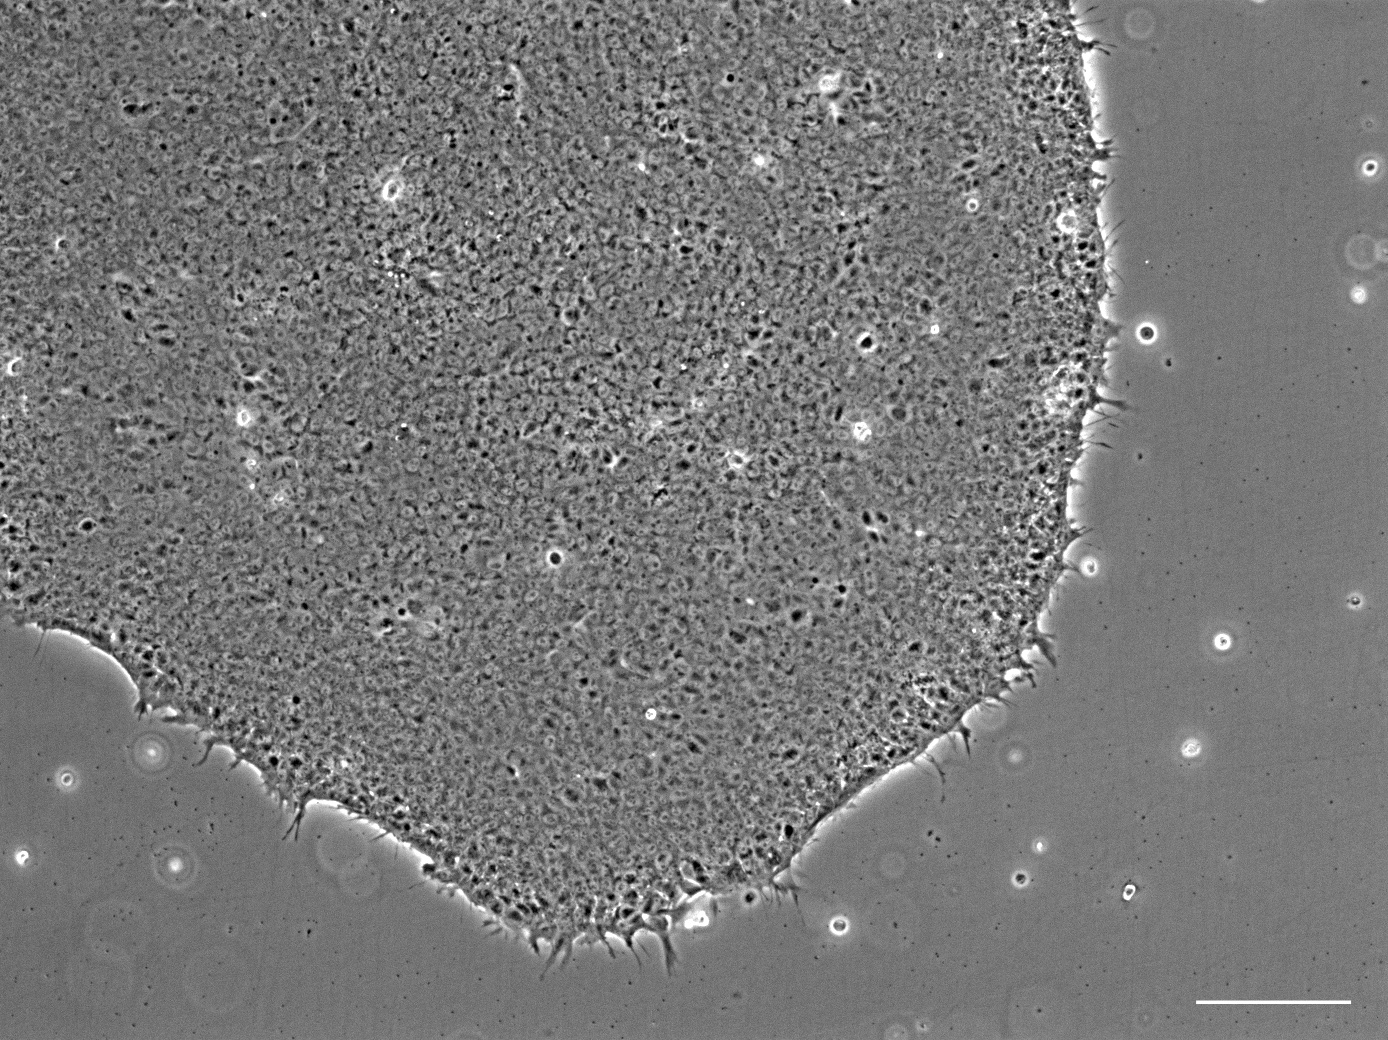

In PHOENIX, NMI provides advanced microelectrode sensor chips and human induced pluripotent stem cell–based disease models that form the basis of the project’s heart and neuromuscular organ-on-chip platforms. NMI also develops upgraded satellite products, including gene-edited cell lines for commercialization, and supports partners with expertise in recording and interpreting electrical and contractile activity of the miniaturised tissues. Finally, NMI leads the industrial qualification of the high-throughput PHOENIX platforms, validating them as reliable tools for drug safety testing and for evaluating new therapies for laminopathies and Friedreich’s ataxia in collaboration with clinical and industrial partners.

Dr. Martin Kriebel – Generation of hiPSC derived disease model cell lines